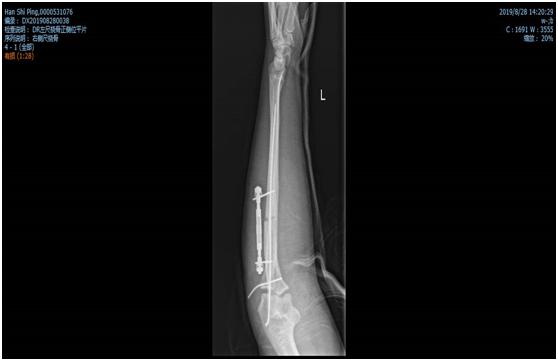

双侧股骨干骨折术前照片

经过骨二科全科人员的商讨后,全麻下行闭合复位髓内钉内固定术的手术方案基本确定。但就国内目前而言,有关髓内钉固定治疗骨骼未成熟的股骨干骨折的疗效研究的样本较小。而且,孩子身高仅160cm,形体偏瘦,测量股骨髓腔最细处约6-7mm,而成人最细髓内钉髓直径大约9mm,无法使用。王钦楠主任积极联系厂家及器械公司,适合的髓内钉终于及时到位,在克服一系列困难及相关科室的支持下,作为威海市首例、山东省第二例同类手术,顺利完成,患者目前已开始负重功能锻炼,病情恢复良好。

双侧股骨干骨折术后照片